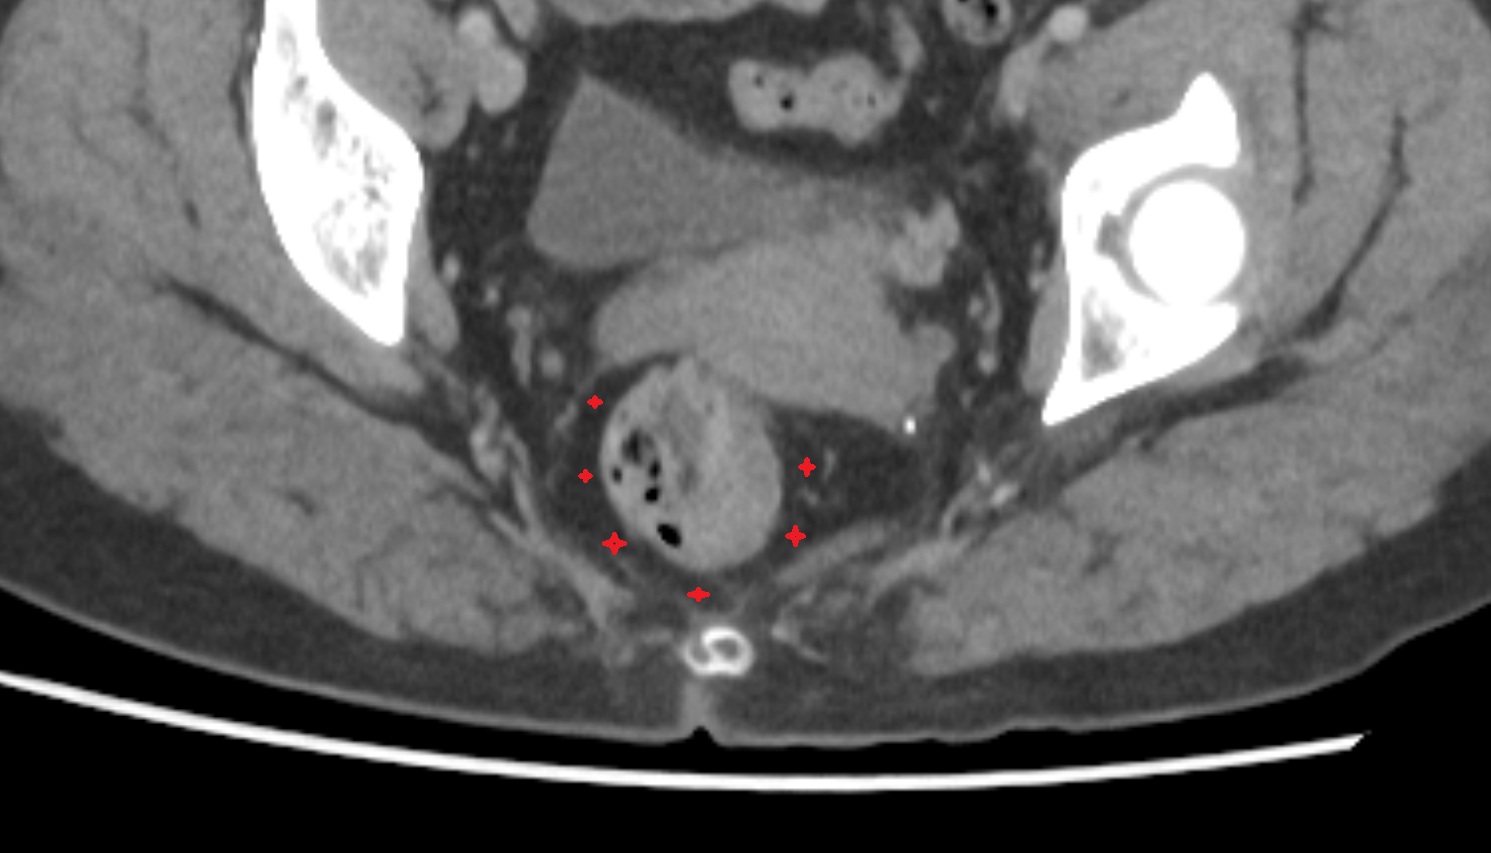

- Peripheral zone of prostate

- Anterior Fibromuscular Stroma of prostate

- Central zone of prostate

- Transitional zone of prostate